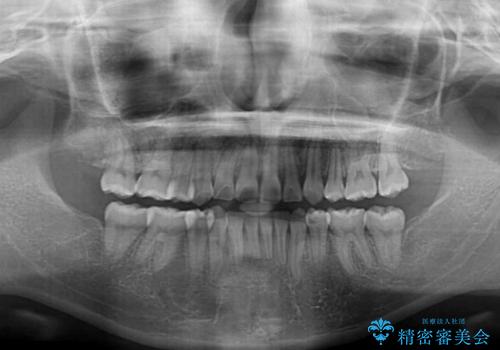

- 上下前歯の叢生と八重歯を気にして来院された患者様です。

前歯部叢生のスペースを獲得するため、上下顎左右小臼歯各1歯を抜歯することとしました。

歯列はきれいに整いますが、歯肉ラインは治療前の歯肉の位置を踏襲します。

特に八重歯であった歯は歯冠が長く見えますので、改善を希望される場合には、歯肉移植術を行う必要があります。